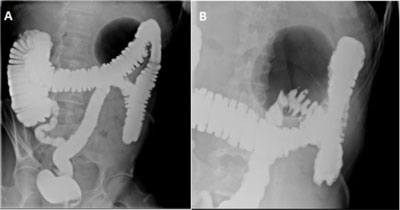

Figure 2

Gastrografin enema in standing position shows (A) a well-defined large gas-filled cavity of 9.7 cm in the left hypochondrium with neither air-fluid level nor extravasation of the contrast agent (balloon sign) and (B) focalized diverticular disease.

In our case the balloon sign was associated with lifting of the sigmoid out of the lower abdomen to the left hypochondrium. Enemas/abdominal X-ray are not necessary if CT scan is available. They typically show a well-defined large gas-filled cyst, with regular and smooth walls and can present an air-fluid level if communicating with the bowel lumen. Colonoscopy is generally avoided because of the risk of perforation.